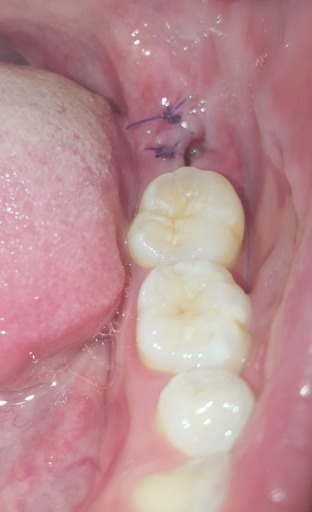

Ever since my wisdom tooth got infected two weeks ago I have had a sore throat that has not gone away. I also have what appears to be a very dont' know if this helps any, but I am a dental student. it is quite common to have swelling after extractions, especially 3rd molar (wisdom teeth) extractions.

Wisdom teeth removal is usually recommended when other treatments haven't worked. How wisdom teeth are removed. Your dentist may remove your wisdom Read more about how a wisdom tooth is removed and recovering from wisdom tooth removal. Possible complications. As with all

Wisdom teeth are the molars (back teeth) that come through last, usually in your late teens or early 20s. This is a normal part of mouth development. Your oral health professional will talk with you about how to care for your mouth after having a wisdom tooth taken out.